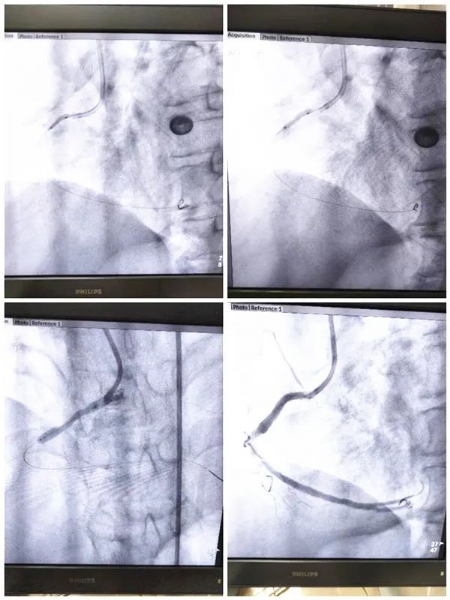

在整个抢救过程中,所有医护人员各司其职,抢救工作高效、有序进行,通过电除颤等一系列的抢救措施,患者生命体征相对稳定。阚国庆主任与患者家属沟通病情,结合患者疾病特点,应立即行急诊冠脉造影及急诊冠状动脉支架植入术,否则患者随时存在生命危险,患者家属表示知情并理解,同意进行手术治疗。遂将患者立即平稳转运至导管室行术前准备,同时麻醉科团队也迅速到位做好手术保障工作。造影示:前降支中段70%—80%狭窄,右冠开口100%闭塞,立即开通闭塞的右冠,给予充分缺血预适应,患者血管开通后,多次出现室性心动过速、室颤,先后给予11次电除颤,并根据心率、血压及时调整药物,待患者心率、血压稳定后,于右冠近段置入支架1枚。由于患者心肌梗死面积大,为了更好地避免心力衰竭及其他器官灌注不足,术后立即置入主动脉球囊反搏泵(IABP)以减轻心脏负荷、保证重要脏器血液灌注。北京中医药大学东方医院驻我院专家范宗静主任给予患者床旁心脏彩超检查评估病情并指导治疗,经过治疗患者安全转出ICU到心血管病房继续治疗,在病房患者感谢阚国庆主任紧紧握住他的手不能松开,还给阚主任点赞,这一握手是患者对我们的感谢、对医护人员工作的肯定,也是我们一直奋斗的动力源泉。